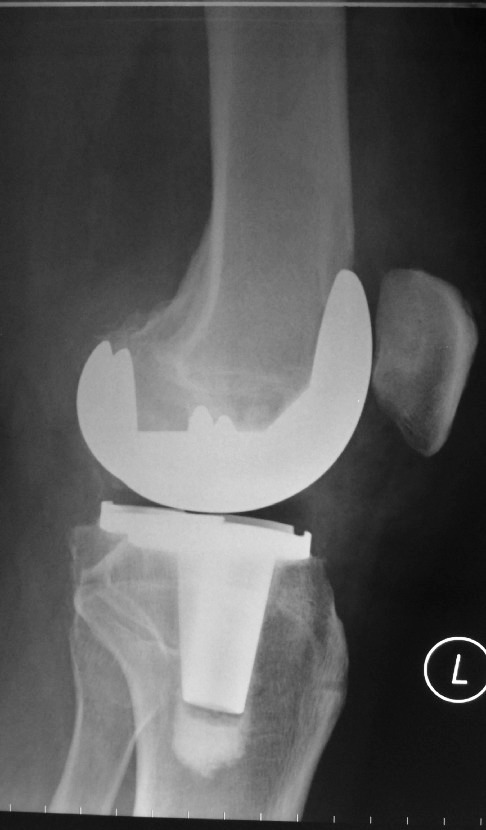

A 60 year old man with painful knee osteoarthritis underwent left total knee replacement using the Zimmer’s iASSIST navigation device.

The check x-rays showed excellent alignment